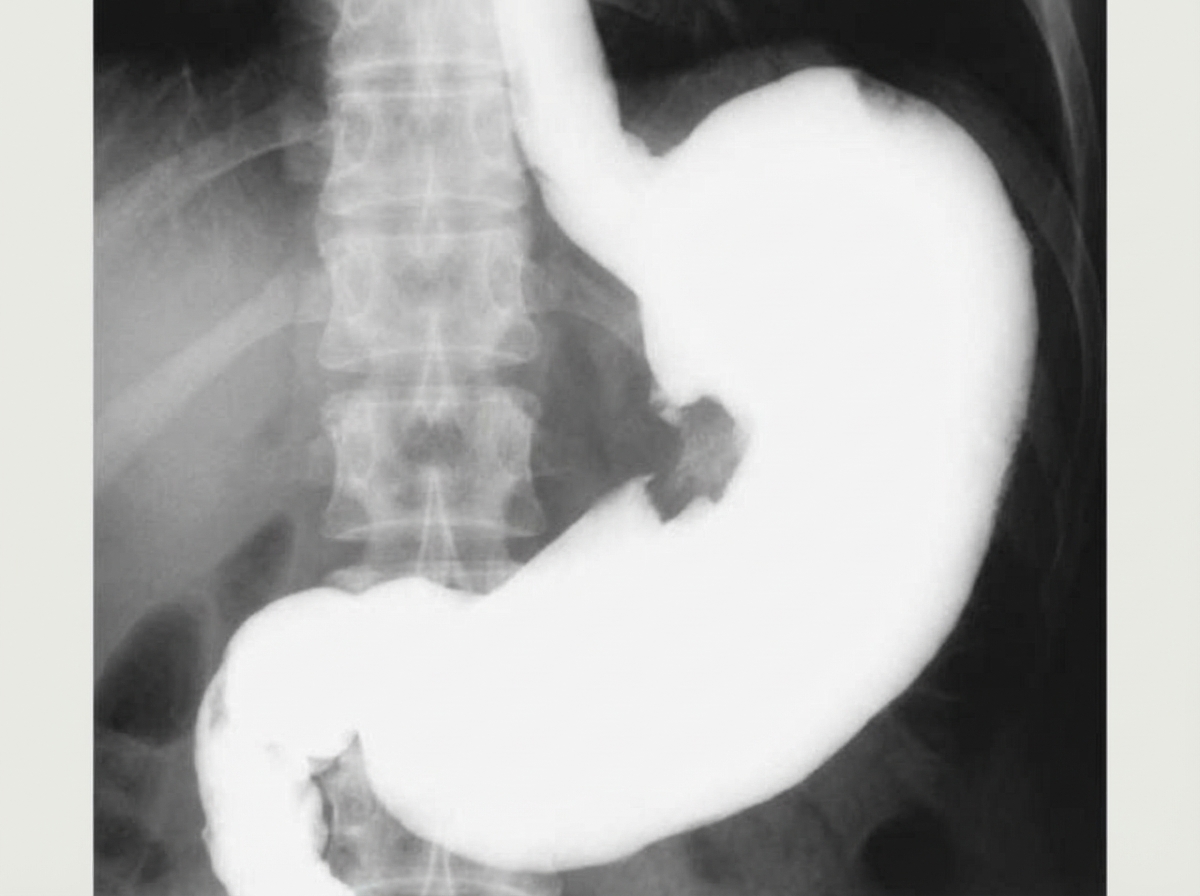

What is indicated by the arrow in the contrast X-ray abdomen?

Explanation: ***Gastric ulcer*** - Shows the classic **niche sign** on barium meal X-ray, appearing as a contrast-filled crater projecting beyond the normal gastric contour. - **Hampton's line** (thin radiolucent line at the base) and **mucosal folds radiating** toward the ulcer crater are characteristic features. *GIST* - Appears as a **submucosal filling defect** with smooth, well-defined margins on contrast studies. - Lacks the **niche sign** and mucosal fold convergence typical of ulcers, presenting as a mass lesion instead. *Carcinoma stomach* - Shows an **irregular filling defect** with **mucosal destruction** and **shouldering** (abrupt transition from normal to abnormal mucosa). - Demonstrates **loss of normal gastric distensibility** and rugal pattern destruction, unlike the focal crater of an ulcer. *Gastric polyp* - Presents as a **smooth, rounded filling defect** that projects into the gastric lumen without crater formation. - Shows **regular margins** and **mobile appearance** on fluoroscopy, contrasting with the fixed ulcer crater.